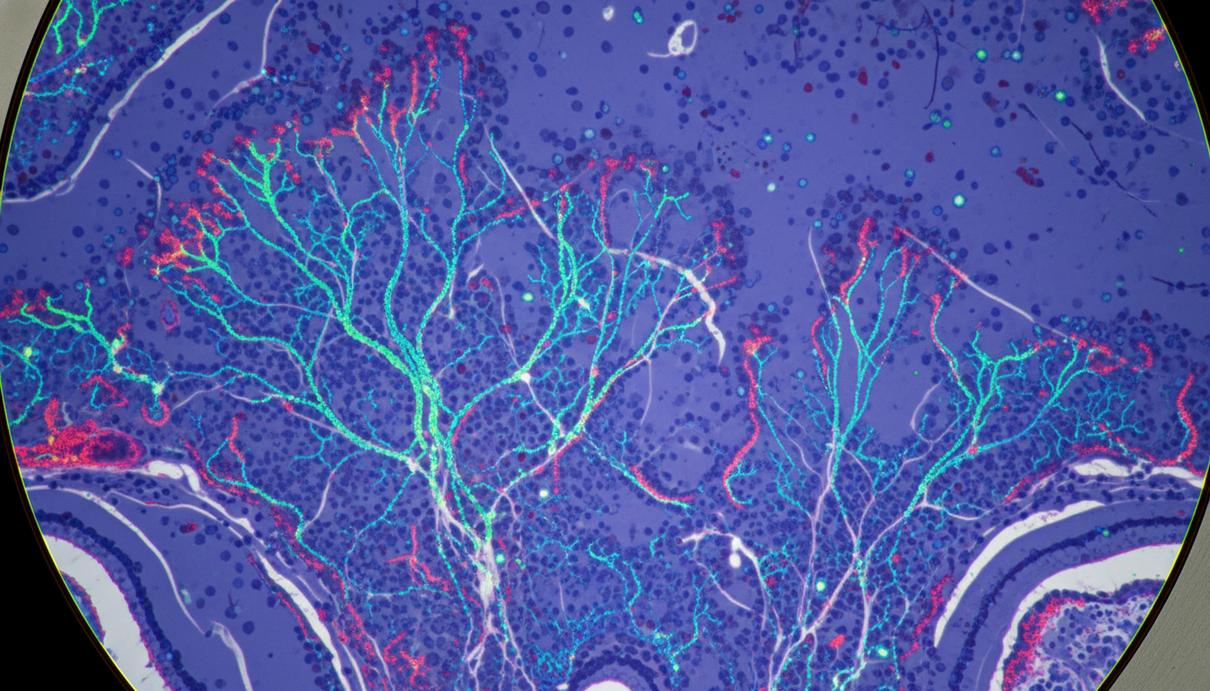

Микроскопическое изображение нейронных сетей мозга с флуоресцентной подсветкой белков в лаборатории.

Лабораторные эксперименты показали, что избыток FTL1 меняет структуру нервных клеток. Вместо разветвленных сетей, характерных для здорового мозга, нейроны формировали упрощенные одиночные отростки. Кроме того, белок негативно влиял на клеточный метаболизм. Однако применение соединений, стимулирующих энергетический обмен, позволило нейтрализовать этот эффект.